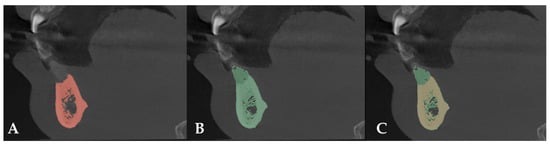

CBCT scans of the entire arch were taken 21 days before surgery and 8 months afterward. CT data were exported in DICOM format. The DICOM data were analyzed using 3DSlicer medical software version 5.2.1 (https://slicer.org accessed on 9 February 2023) [17]. Preoperative and postoperative studies were segmented using the software’s thresholding tool, and the resulting segments were superimposed. The difference between the preoperative and postoperative segments was re-segmented to obtain the graft segment, which was then exported in STL format [18].

After comparing preoperative and postoperative CT images, an increase of 8.80 mm in height and 7.6 mm in bone width was observed. Bone regeneration was confirmed (Figure 6).

Figure 6. (A) Preoperative CT scan. (B) Postoperative CT scan. (C) Superimposition of preoperative and postoperative CT scans.